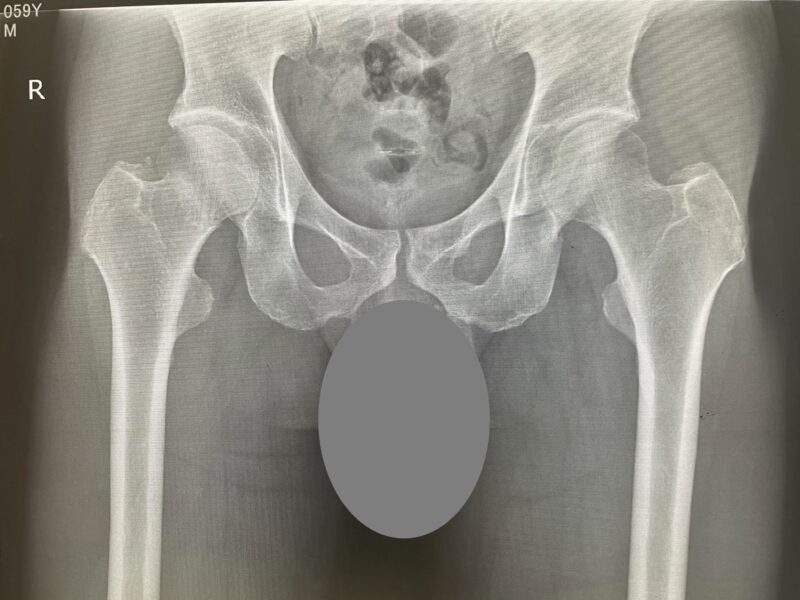

また, 大腿骨頚部骨折に対して人工骨頭挿入術が行われて, リハビリテーション中の高齢の患者さんが, 今日の2時頃にベッドサイドで転倒されてから, 手術をしていない反対側のふとももを痛がっていると夜勤の看護師さんから報告されたので, 診察しました. 痛い方の股関節を自分で動かすことはできましたが, 深く曲げるとふとももの付け根の痛みが出るので, 自分と同じく非転位型の大腿骨頚部骨折を疑いました. X線写真を撮像するようにオーダーを入れました.

同じように大腿骨頚部が外反陥入した骨折でした.

また, 大腿骨人工骨頭挿入術後の高齢患者さんの股関節のX線写真を見たところ, 反対側の大腿骨頚部に自分が受傷したのと同様の外反陥入型の骨折を認めました. ご家族に電話をして, 状況を報告しました. 学会で出張中の後輩医師が主治医となっているので, 出張から戻ってきた後に治療方針(手術しないで安静を保って骨がつながるのを待つか, 手術療法を行うか, 手術を行うとすると, 骨を器械でつなげる手術(内固定術)か人工骨頭挿入術か)を決定して, また連絡することになりました.